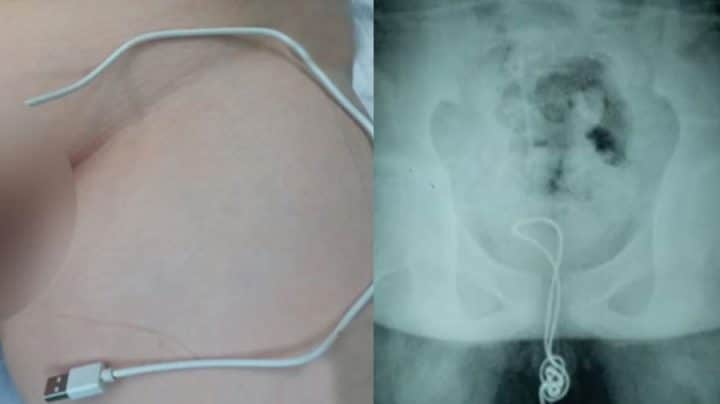

Un garçon de 13 ans est arrivé à l’hôpital avec des douleurs au pénis. Pas besoin de faire beaucoup d’examens pour comprendre ce qu’il lui était arrivé. De son méat pendait un câble USB Apple qu’on utilise pour recharger un iPhone. Les médias qualifient ce garçon de « curieux ». En jouant avec son sexe, il a inséré le bout le plus fin du câble dans le méat, et l’a enfoncé dans son urètre. Regardez la vidéo pour voir les scanners de ce pauvre garçon.

Le jeune adolescent est arrivé tout penaud à l’hôpital, accompagné de ses parents. Ils se sont rendus aux urgences du comté de Linkou, au nord-est de la Chine, dans la province de Heilongjiang. Il a suffi de montrer son entrejambe deux secondes pour que les médecins comprennent la raison de ses douleurs. Mais c’est en faisant une radio de la zone, qu’ils se sont rendus compte de l’ampleur des dégâts.

Il avait inséré un câble USB dans son urètre

Si l’une des extrémités d’un câble USB Apple est suffisamment fine pour entrer dans un pénis, cela devient plus embêtant lorsque le câble finit par bloquer la sortie. Il s’est enroulé à l’intérieur de son urètre, créant un nœud et empêchant de l’enlever. À peu près 20 centimètres de câble étaient insérés dans l’urètre, atteignant même la vessie. C’est en touchant la vessie que l’enfant a senti de vives douleurs. Le médecins de cet hôpital n’ont pas voulu se risquer à l’opérer et l’ont donc transféré à l’Hôpital pour enfant de Harbin. Le docteur Xu Liyan, urologue à l’hôpital a commenté ce cas : « Le câble avait atteint la vessie où il s’était emmêlé et a formé un nœud. En forçant pour le sortir, ça l’a coincé. » Pour le délivrer, ils ont dû couper le câble et inciser la vessie pour le tirer dans ce sens. Lorsque ses parents lui ont demandé pourquoi il avait fait ça, l’enfant en pleine puberté a simplement expliqué qu’il était « curieux » d’essayer. Cette histoire nous rappelle celle de cet homme qui avait enfoncé une baguette chinoise dans son pénis.